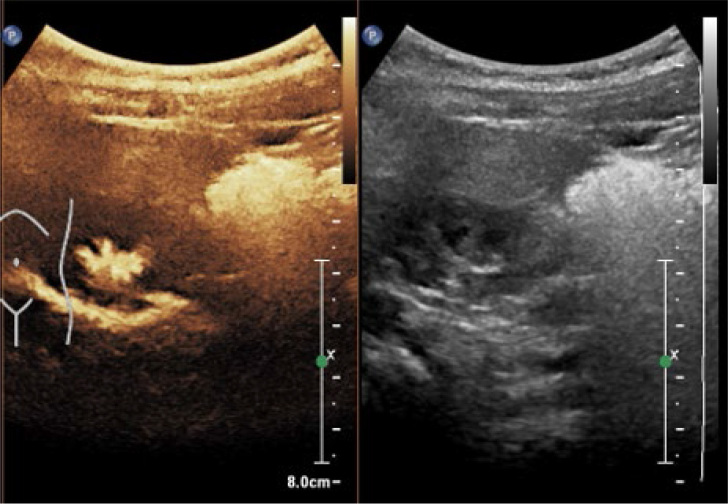

Conclusions: RBUS effectively diagnoses duplex kidneys with renal pelvic dilation, while ceVUS can further elucidate whether reflux occurs in the upper or lower moiety in cases of duplex kidneys with VUR. Compared to VCUG, both RBUS and ceVUS provide more intuitive diagnoses for duplex kidneys with VUR and ureterocele. Additionally, there is good consistency between ceVUS and VCUG in grading VUR. CeVUS is recommended as an initial evaluation method for patients suspected of having duplex kidneys associated with urinary tract infections.

Abstract Image